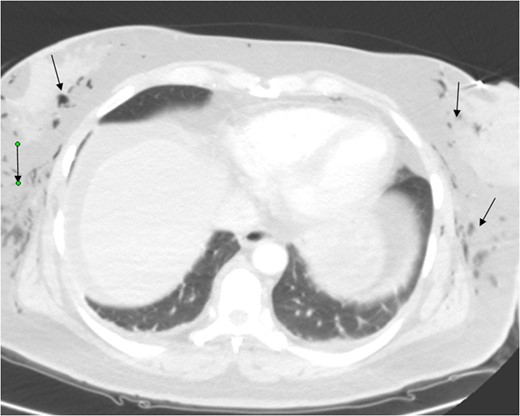

A 46-year-old female, Gravida 3 para 3, all alive, with past medical history of depression, acid reflux and uterine fibroids presented to our emergency unit with acute exacerbation of lower abdominal pain, vaginal bleeding and dizziness, which she had for a month. On examination, her abdomen was soft, with tenderness to right and left lower quadrants. Pelvic examination showed a 14-week uterus, per vaginal bleed and closed cervical os. A repeat sonogram showed the uterus to be 13.9 × 4.8 × 7.1 cm3 with three dominant intramural fibroids. Fundal fibroid measured 3.3 cm, mid posterior uterine fibroid measured 2.2 cm and mid/lower uterine fibroid, 3.8 cm. The central endometrial echo was normal. The right ovary measured ~2.5 × 1.7 × 3.0 cm3 while the left ovary, was 2.5 × 1.9 × 1.7 cm3. Her hematocrit and hemoglobin on presentation were 32% and 11 g/dl, respectively, down from 42% and 14 g/dl a week earlier. She was scheduled for laparoscopic-assisted vaginal supra-cevical hysterectomy with bilateral salpingo-oophorectomy. The operative technique required placing the patient in steep Trendelenburg position and use of a Veress needle through an umbilical incision for insufflation of 3 l of carbon dioxide at a pressure of 15–20 mmHg. All trocal placements were done without complications. Estimated blood loss was 700 ml. The operative time was 7 h (420 min). Surgery was complicated with carbon dioxide overload and retention, with partial pressure of carbon dioxide (PCO2) of 67 mm of mercury (mmHg) immediately post operatively. Patient developed extensive subcutaneous emphysema, and pneumomediastinum (Figs 1–3) on first post-operative Day 1, requiring intubation and mechanical ventilation. Her minute ventilation was increased to wash off the excess CO2. She was sedated and managed expectantly with observation and watchful waiting in the intensive unit. Both subcutaneous emphysema and pneumomediastinum resolved spontaneously by post-operative Day 3 with non-operative treatment. She was eventually discharged in stable condition on post-operative Day 3 and followed up in clinic with no residual issues.

Pneumomediastinum and subcutaneous emphysema as indicated by the arrows.